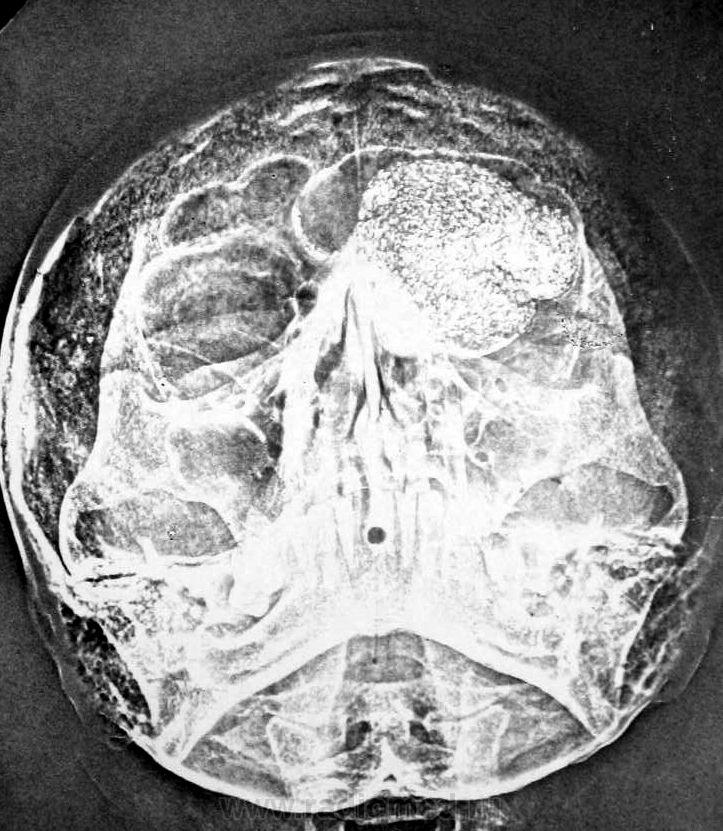

Гигантская остеома лобной пазухи. Лет 25 назад видела одну такую, может даже чуть побольше. Больше ничего похожего не попадалось.

Плотность-то костная.

Согласен,гигантская губчатая остеома

При мукоцелле, может быть кальцинация по периферии, такой гомогенной кальцинации не будет. Это остеома.

В моем случае пазуха также была значительно растянута. Случай верифицирован. Больная была прооперирована, у нее также был экзофтальм.